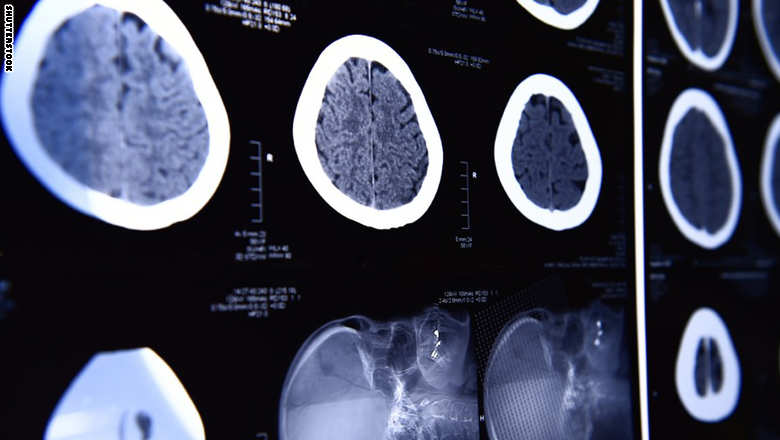

ونظرت دراسة جديدة في أكثر من 70 ورقة علمية حول مسح الدماغ مثل التصوير بالرنين المغناطيسي الوظيفي والكهربائي والاختبارات التي تقيس نشاط الدماغ. وخلصت الدراسة إلى أن نسبة النجاح لدى الأطباء تزيد خلال مرحلة علاج بعض المرضى، وذلك إذا قاموا بفحص كيفية عمل وظيفة الدماغ لدى شخص ما.

واستخدم مسح الدماغ لاكتشاف السلوك البشري لعقود من الزمن، ولكن لا يتم طلب هذا المسح بشكل روتيني، لتحديد الحالة الصحية العامة للمرضى، أو مسار العلاج، مقارنة بالوتيرة التي يطلب فيها الأطباء إجراء فحوصات دم للمرضى.

وأشارت الدراسة الجديدة إلى أن التكنولوجيا في هذا المجال أصبحت متقدمة جداً، حيث أن المقاربة إلى العلاج ستكون أكثر فعالية، إذا استخدم مسح الدماغ بشكل روتيني أكبر.